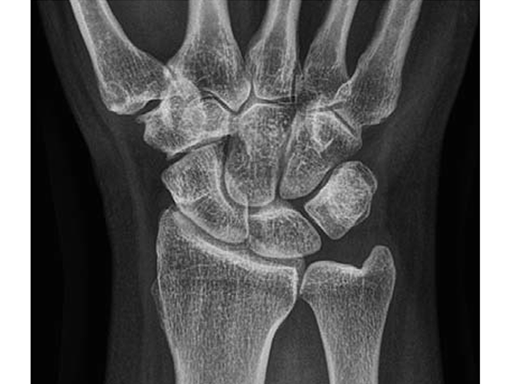

Case 2: Painful ulno-carpal abutment

A 32-year-old man suffered torsional trauma about the right wrist, with TCFF rupture. A failed arthroscopic repair had taken place. Constitutional ulna plus. Symptoms included pain and impaired function about the wrist and forearm. Painful DRUJ (DASH: 22, PWRE: 21).